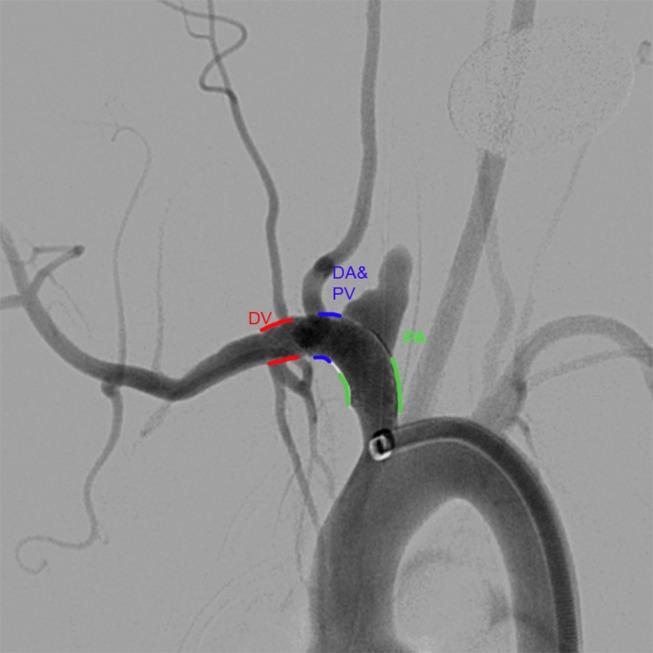

Thromboembolic complications remain a limitation of flow diverting stents. We hypothesize that phosphorilcholine surface modified flow diverters (Pipeline Flex with Shield Technology, sPED) would have less acute thrombus formation on the device surface compared with the classic Pipeline Embolization device (cPED).

Elastase-induced aneurysms were created in 40 rabbits and randomly assigned to receive cPED or sPED devices with and without dual antiplatelet therapy (DAPT) (four groups, n=10/group). Angioplasty was performed to enhance apposition and create intimal injury for a pro-thrombotic environment. Both before and after angioplasty, the flow diverter was imaged with intravascular optical coherence tomography. The outcome measure was the number of predefined segments along the implant relative to the location of the aneurysm with a minimum of 0 (no clot formation) and maximum of 3 (all segments with thrombus). Clot formation over the device at ostia of branch arteries was assessed as either present or absent.

Following angioplasty, the number of flow diverter segments with clots was significantly associated with the flow diverter (p<0.0001), but not with DAPT (p=0.3872) or aneurysm neck size (p=0.8555). The incidence rate for clots with cPED was 1.72 times more than with sPED. The clots on the flow diverter at the location corresponding to side branch ostia was significantly lower with sPED than with cPED (OR 0.180; 95% CI 0.044 to 0.734; p=0.0168), but was not associated with DAPT (p=0.3198).